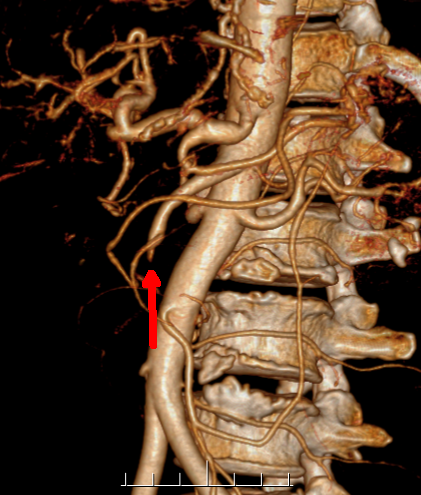

▲ 肠系膜CTA提示肠系膜上动脉病变

吴万庆副主任医师接诊后根据郭师傅病情立即给予手法复位及临床对症处理,然而患者腹痛虽一时缓解,而后再次加剧。吴万庆副主任医师立即安排肠系膜血管CTA检查,结果显示:肠系膜上动脉中段螺旋状改变,显影极浅淡,证实已经继发肠系膜血管问题。